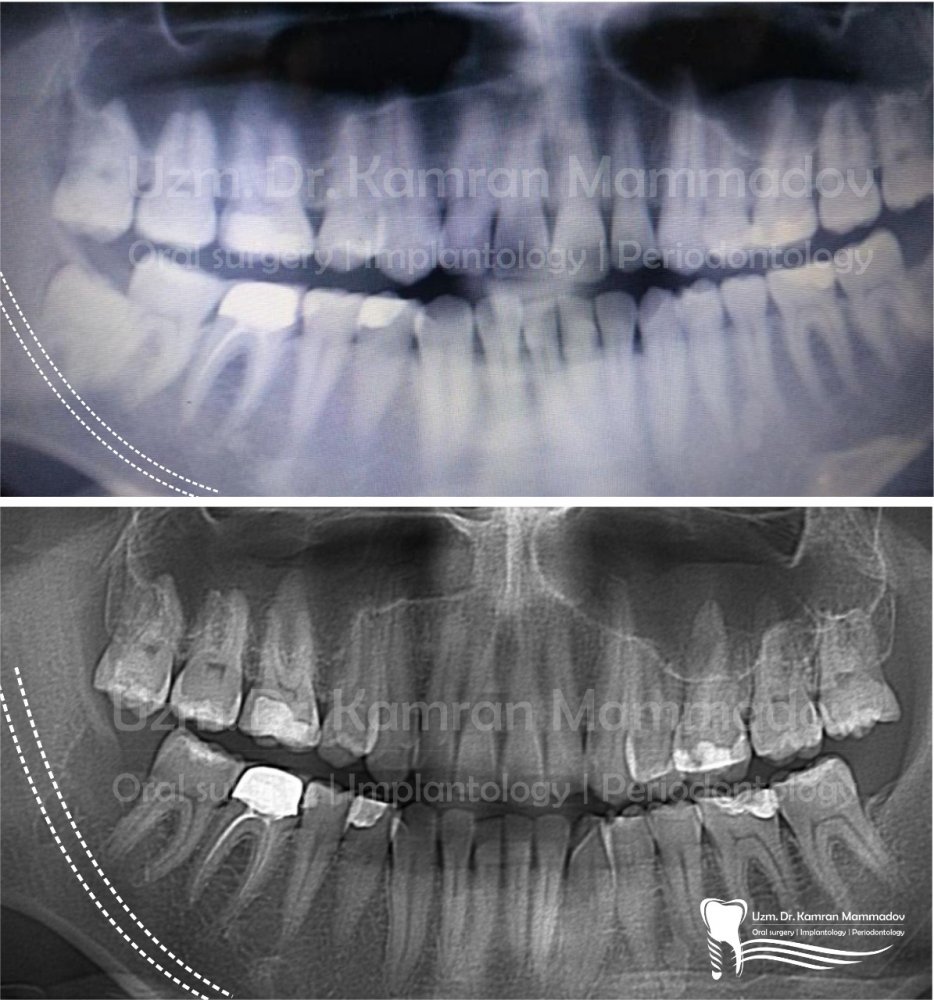

Normal halda insanın diş sırasında hər çənədə iki ədəd olmaqla, ümumilikdə dörd agıl dişi mövcuddur. Ağıl dişinin çıxması bəzi şəxslərdə heç bir kliniki əlamət və ya şikayətə səbəb olmasa da, bir çox hallarda müəyyən kliniki əlamətlərlə öyünü biruzə verir. Bu əlamətlər əsasən çənənin arxa tərəfində təzyiq, çənəni açıb baglama əsnasında agrı və məhdudlaşma kimi özünü göstərə bilir. Bu hallarda mütəxəssis konsultasiyasının önəmi olduqca böyükdür. Belə ki müayinə zamanı cərrah-stomatoloq kliniki və radioloji dəyərləndirmə apararaq dişin dogru pozisiyada yerləşib yerləşmədiyi, dişləmə çıxma ehtimalını, agıl dişinin çənəyə görə ölçüsü və çənə darlıgı kimi durumları dəyərləndirərək tətbiq edilməli olan müalicə taktikasını müəyyən edir.